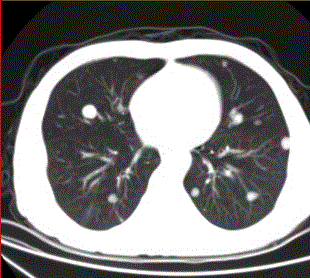

问题 患者男,45岁,因肝硬化、肝癌行肝移植术后6个月,咳嗽2周,来院复查。CR及CT影像如下图。 肺内转移结节可为

选项 A.弥漫性粟粒结节 B.单发结节 C.结节发生坏死形成空洞 D.钙化结节 E.带毛刺的结节 F.含脂肪成分的结节

答案 ABCDE

解析 ABCDE